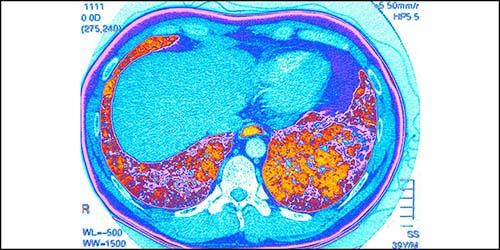

Clinicians from Columbia and Weill Cornell Medicine are at the forefront of pulmonary medicine and lung surgery combine leading-edge therapies with compassionate care for patients with all types and stages of lung disease. Our researchers are contributing to promising advances in acute lung injury, COPD, interstitial lung disease, and pulmonary hypertension.

Pulmonology & Lung Surgery